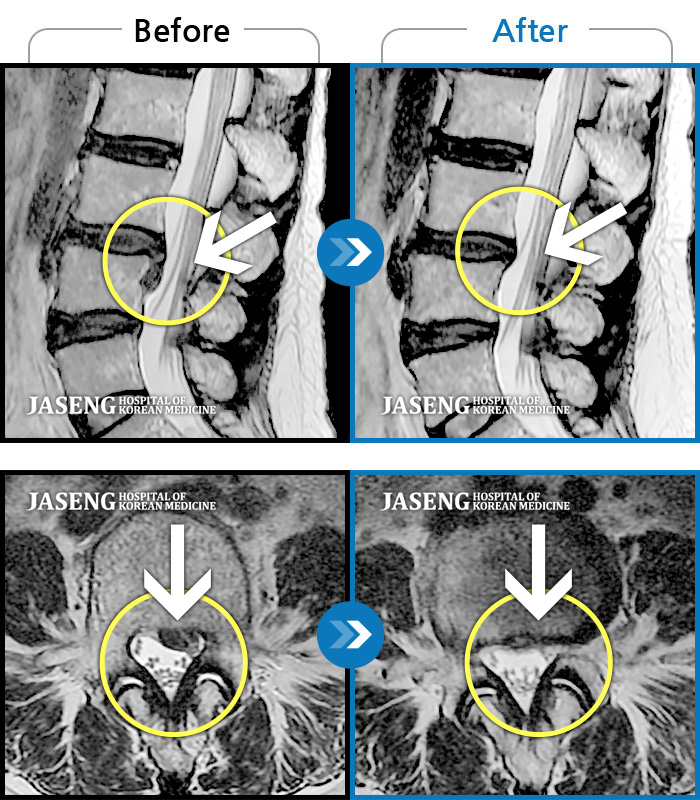

Before

After

환자에게 사전 동의를 받아 동일 조건에서 촬영되었습니다.

개인에 따라 치료 후 부작용이 발생할 수 있으니 의료진과 상담 후 치료를 진행하시기 바랍니다.

요통과 다리 통증